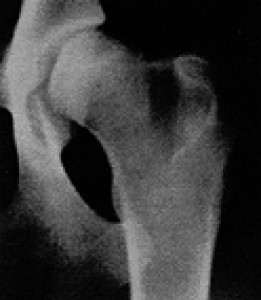

Provádění rtg snímku DKK: